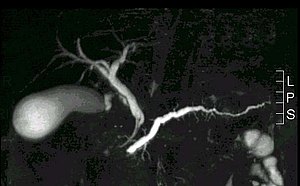

gestauter_pankreasgnagn_bei_Krebs.jpg

gestauter Pankreasgang bei Krebs